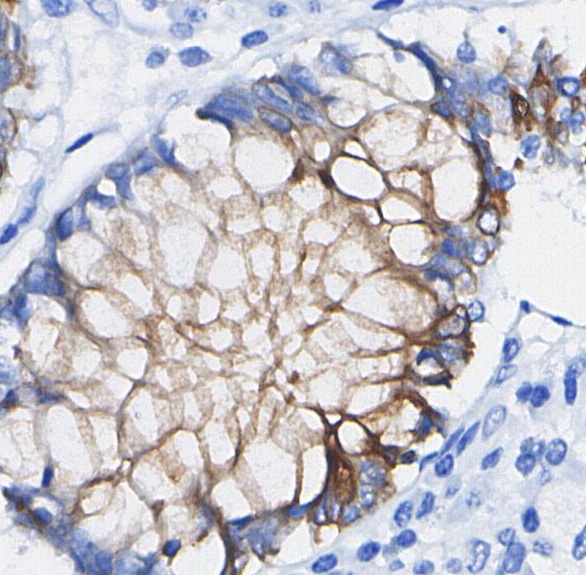

• Immunohistochemical analysis of formalin fixed paraffin embedded human Colorectal cancer tissue with F1694 at 1/100 dilution.

Integrin α2 Antibody [B7L6] recognizes endogenous levels of total Integrin α 2 protein.

Integrin alpha 2 (Integrin α2, CD49b) is a vital adhesion receptor that forms a heterodimer with integrin β1, creating the α2β1 integrin complex. This receptor is integral to interactions with various extracellular matrix (ECM) components, such as collagen, laminin, and fibronectin. It is crucial for cell adhesion, migration, and force generation within the ECM, and plays a significant role in processes like platelet aggregation and stem cell differentiation. The α2β1 integrin also influences gene expression related to collagen and ECM remodeling. Aberrations in integrin α2 expression and function are associated with pathological conditions, including cancer, where it contributes to tumor progression and metastasis by affecting cell behavior and interactions with the ECM.